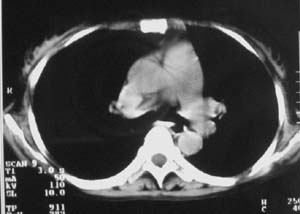

以下是引用zjzjr在2007-9-20 12:29:00的发言:[br]双肺磨玻璃改变,考虑肺水肿.

以下是引用yangzongshan在2007-9-20 18:29:00的发言:[br]两肺毛玻璃样改变,其内可见肺纹理影,无胸腔积液,故考虑肺泡蛋白沉积症

以下是引用276894491在2007-9-20 13:40:00的发言:[br]考虑肺水肿;外源性过敏性肺炎不排除。

以下是引用逸风在2007-9-20 20:45:00的发言:[br]两肺磨玻璃样改变,临床病史短,发热,考虑病毒感染合并右肺代偿性肺气肿.待排肺水肿,病史短,不支持肺泡蛋白沉着症.